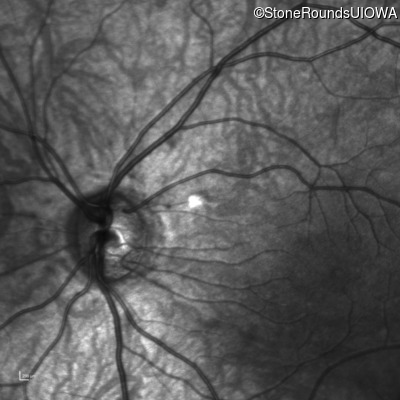

Infrared Fundus Photograph - Right - 10/160 sc

Exemplar